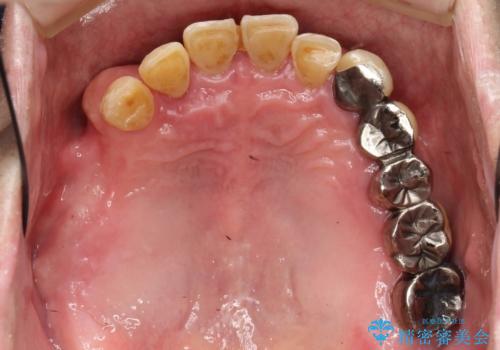

虫歯だらけ、歯周病 崩壊した口腔の再建 フルマウスリコンストラクション

- 歯周外科・インプラント・顕微鏡下根管治療などを含んだ総合的な治療を計画した。

かみ合わせの力が非常に強く、夜間の歯ぎしり・食いしばりもひどかったため、奥歯はメタルオクルーザルの設計でかぶせ物を製作しています。

かぶせ物の種類:PFZ / PFM metal occlusal